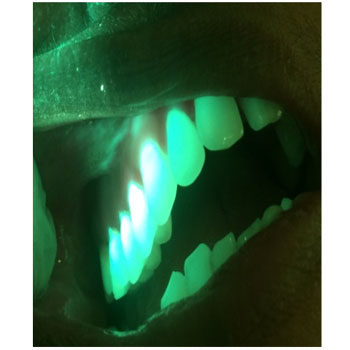

The intensity adjustability of the light gives additional advantage to the device in oral cavity where reflection with saliva and adjacent teeth is a common scenario .

clinical Image and Image of the lesion Under the influence of Blue light, we can appreciate the difference in the extent of the lesion under white light and blue light. The blue light used with low intensity.

Clinical Image and Blue light image with High intensity of light, Both Images are filtered for better appreciation

With Low intensity of light, with high intensity of light , we can appreciate the reflection with enamel which is adjacent to the lesion, thus masking some part of the lesion